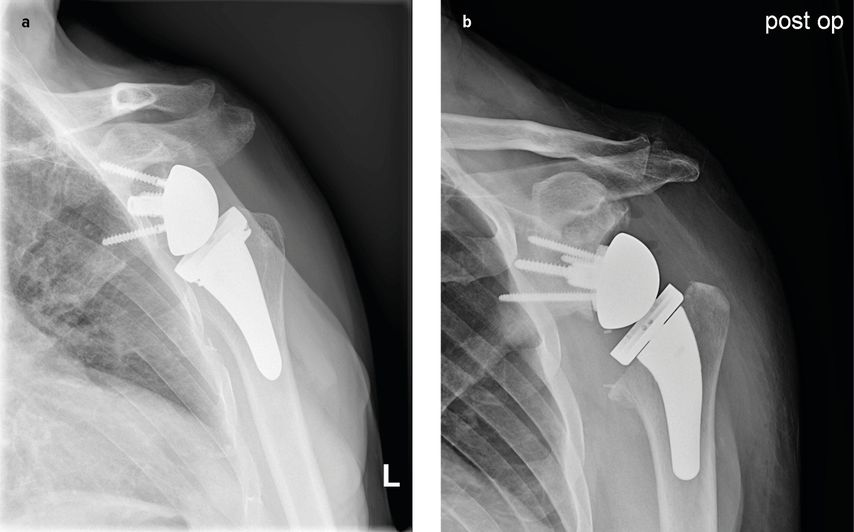

Abb. 3: Arthroskopische Revisionsoperation nach erneuter arthroskopischer Ankerplatzierung

Abb. 5: 5a: Inverse Schultertotalendoprothese mit 2 verschiedenen Implantaten, 5b: zusätzliche knöcherne Metallaugmentation am Glenoid bei knöchernem Defekt